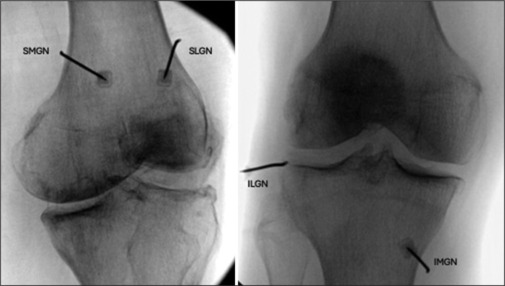

膝关节射频消融术缓解慢性疼痛的预后和预测因素:一项回顾性队列研究。

Outcome and predictors of knee radiofrequency ablation for chronic pain relief: A retrospective cohort study.